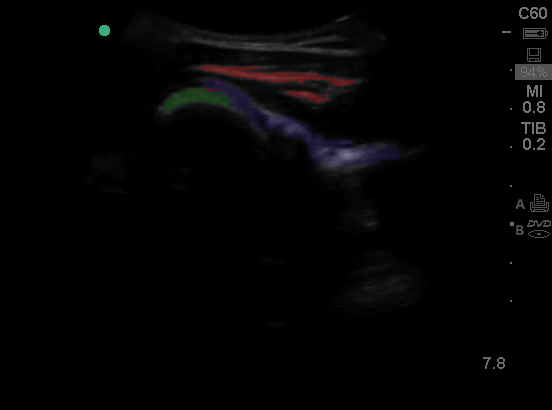

Shoulder dislocations can also be visualized on ultrasound. Start posterior and visualize the humerus then move it upward and medially until you can see the humeral head.

In this picture you can see the rotator cuff (red), humeral head (green) and glenoid (purple).

And here is the shoulder rotating

And what a dislocated shoulder looks like, space between the glenoid and the humeral head.